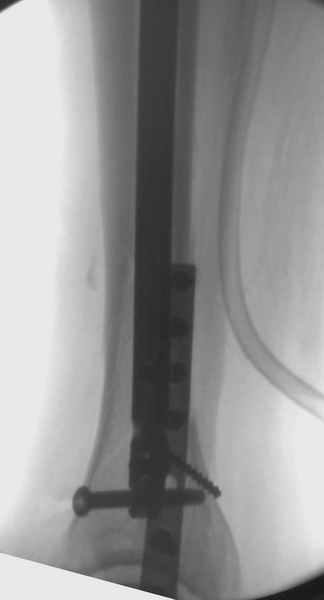

Здесь мы использовали новый Synthes Nail с дополнительными дырками, в проксимальной части 4: по две косых и поперечные (один стандартный а другой динамический), в дистальной части две поперечные, прямая и косая. Вес больного более 120 кг, нагрузку начнем через месяц.